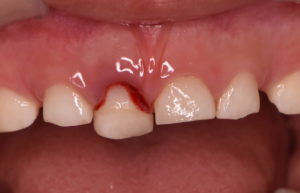

受傷から2週間

脱臼した際に歯の内部の神経・血管に障害が生じるため、内部で充血に伴う歯の変色が生じています。

レントゲン診査でも異常所見はないため、このまま何もせず経過観察を行います。